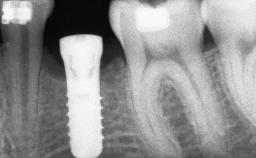

A 47-year-old Caucasian woman with a single-tooth edentulous space at the site of the left maxillary canine was referred for treatment. She had undergone traumatic extraction of this impacted canine several months before referral. Her chief complaint was the dissatisfying appearance of her smile. The patient desired a stable and esthetic rehabilitation of the site. Her dental history showed no evidence of periodontal disease or bruxism. She had no systemic diseases, was not taking any medications, and did not smoke. The extraoral examination revealed a high lip line and an inadequate soft-tissue volume at the defective canine site. Large black triangles were visible between the canine and its adjacent teeth.

Bone Augmentation | Staged|Vertical |

Augmentation Materials | Autogenous chips|Membrane |